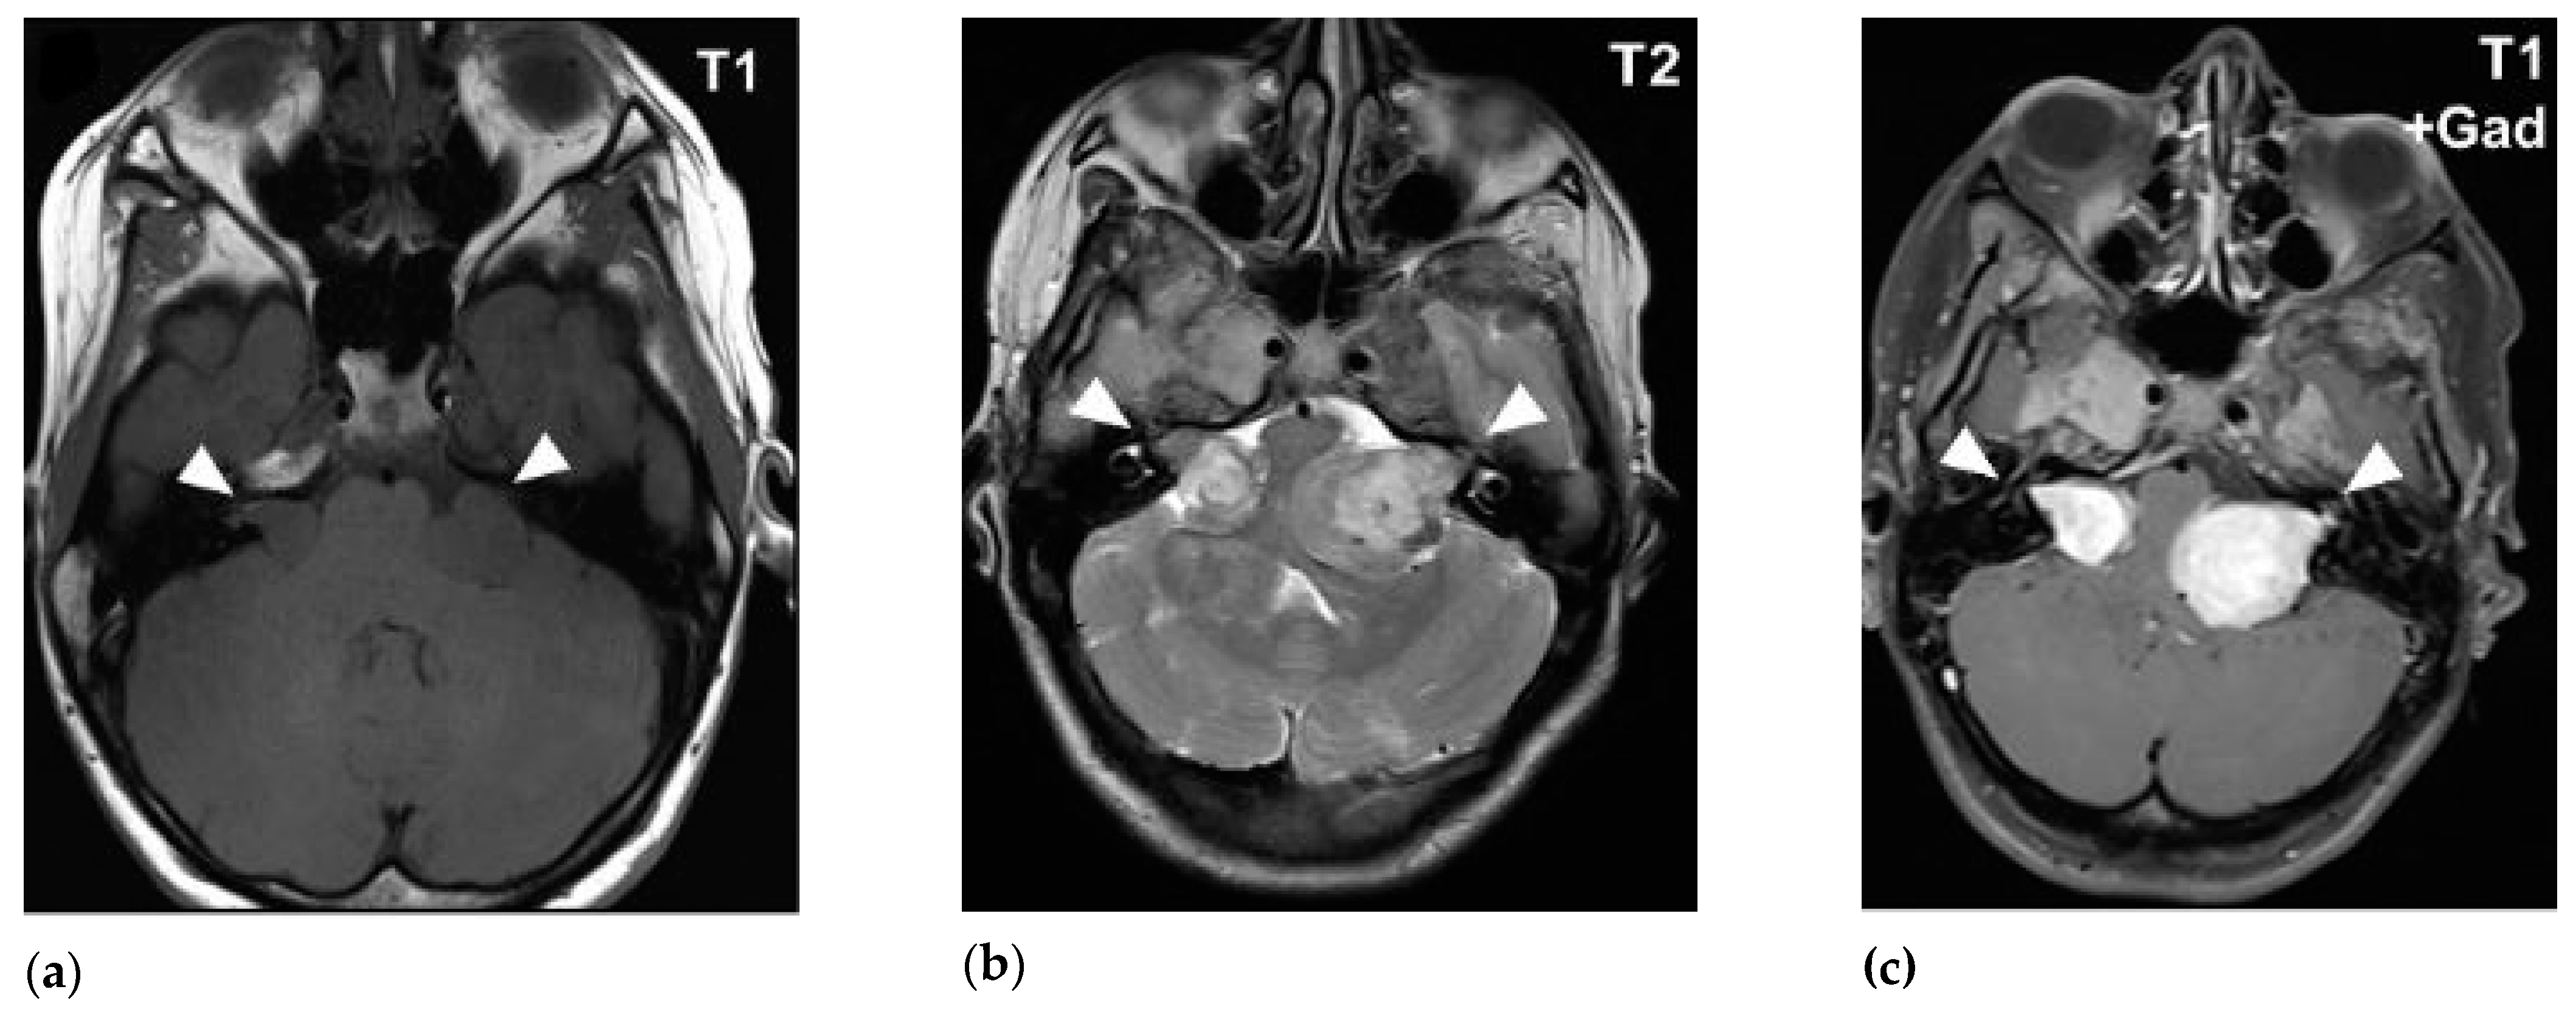

• cortical dysplasia: cortical tuber, cortical white matter migration line

• subependymal nodule: 측뇌실로 돌출되어 촛농모양으로 관찰,석회화 가능

• subependymal giant cell astrocytoma (SEGA)